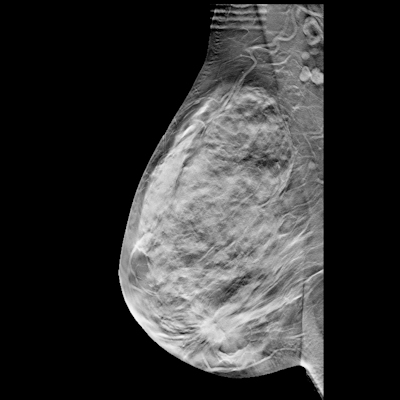

After a multidisciplinary team selected 10 parameters deemed important for oncologic imaging history, the researchers then performed a retrospective study involving 207 patients who had received CT scans at a cancer center. Prompt engineering was performed on 7 patients and then GPT-4 was tasked with generating clinical histories from the designated oncologic parameters extracted from clinical notes for the remaining 200 patients.